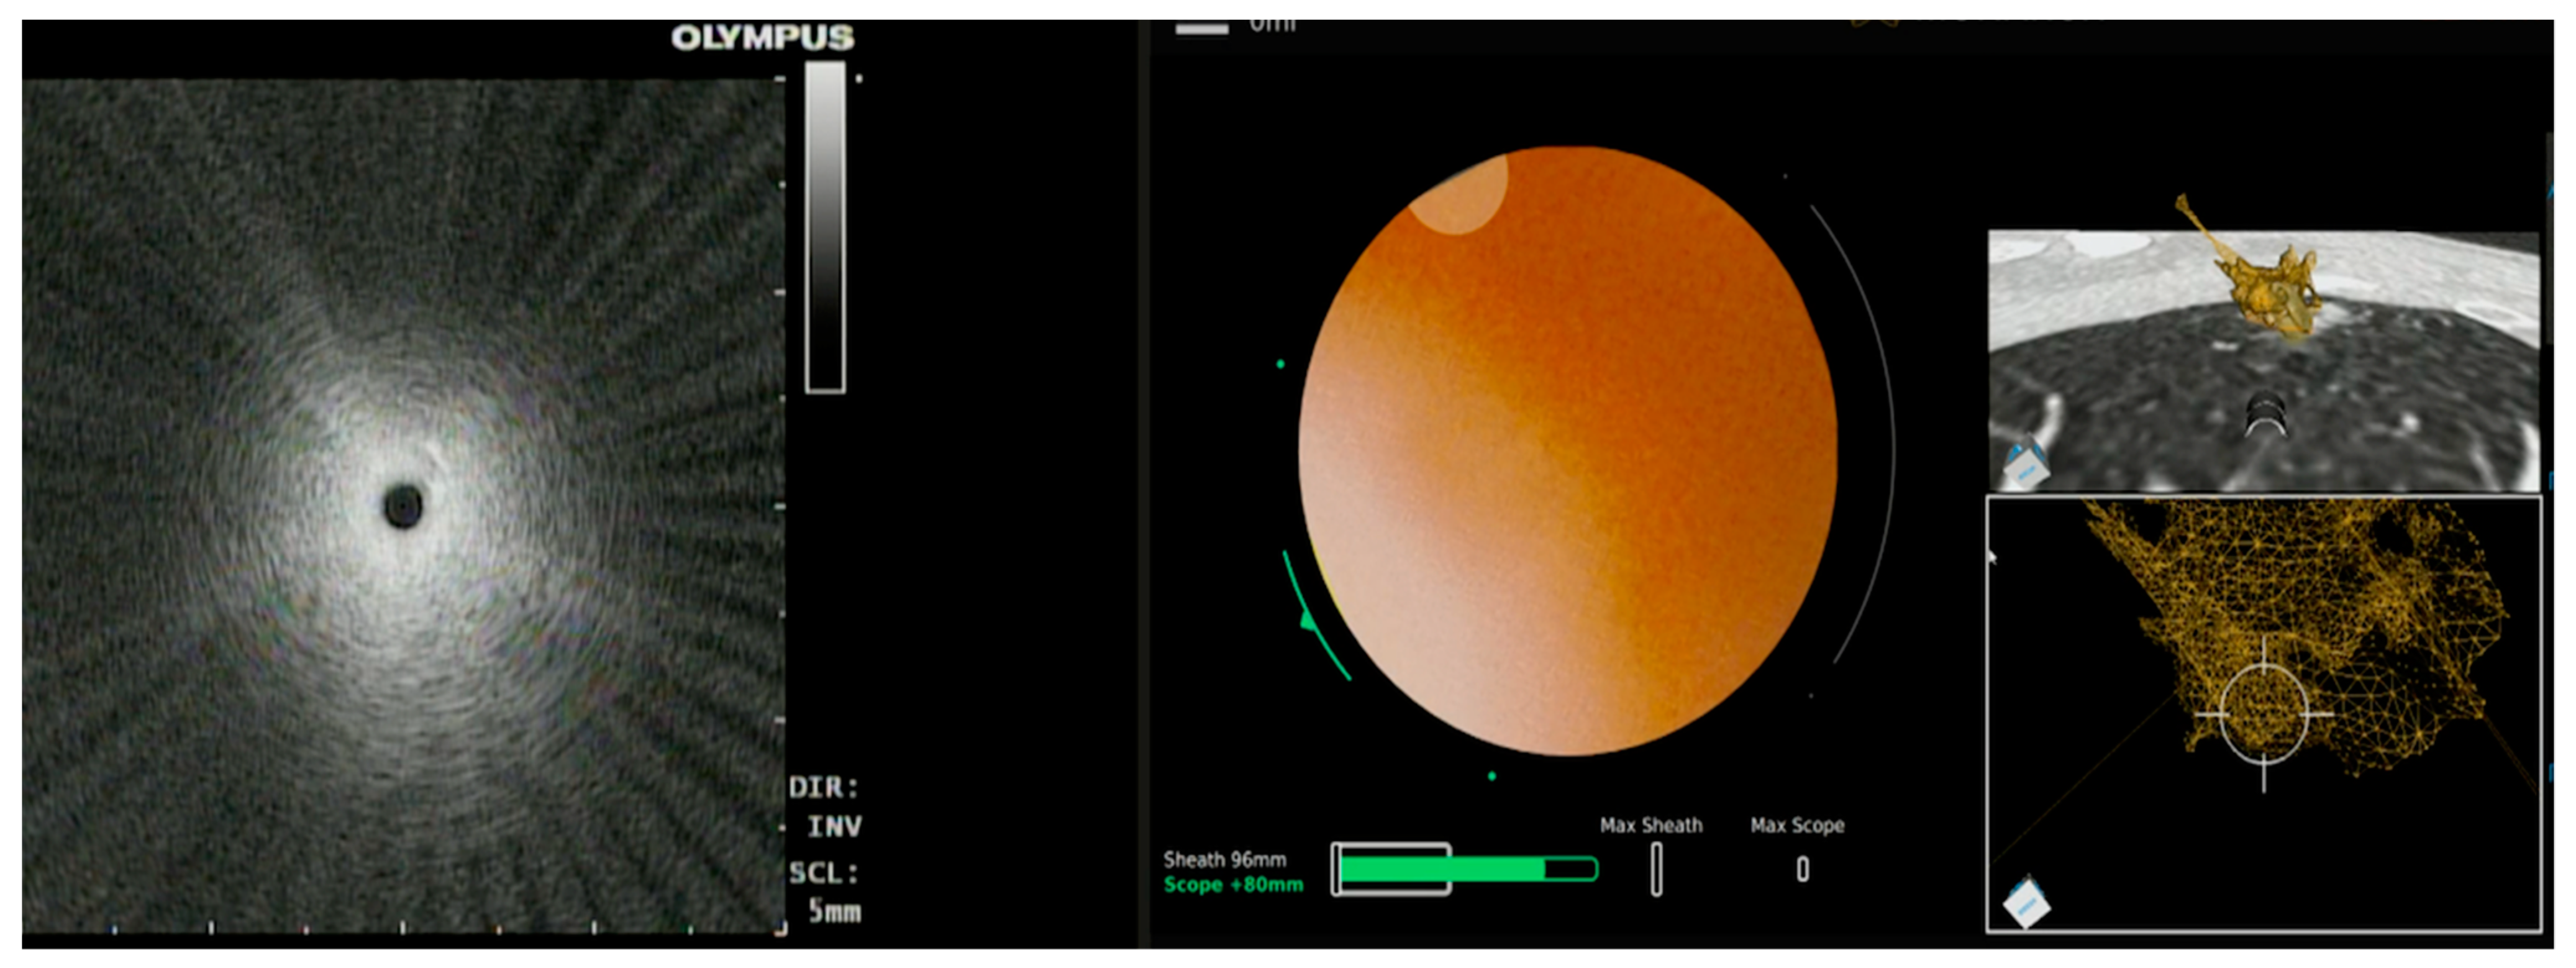

3.2.1. Ion™ Robotic Platform Combined with CBCT

- Folch, E.E.; Pritchett, M.A.; Reisenauer, J.; Casal, R.F.; Simoff, M.J.; Keyes, C.; Diaz-Mendoza, J.I.; Fernandez-Bussy, S.; Majid, A.; Parkih, M. Prospective, multicenter analysis of shape-sensing robotic-assisted bronchoscopy: Updates from the precise study. Chest 2022, 162, A2655–A2656. [Google Scholar] [CrossRef]

- Kalchiem-Dekel, O.; Connolly, J.G.; Lin, I.H.; Husta, B.C.; Adusumilli, P.S.; Beattie, J.A.; Buonocore, D.J.; Dycoco, J.; Fuentes, P.; Jones, D.R.; et al. Shape-Sensing Robotic-Assisted Bronchoscopy in the Diagnosis of Pulmonary Parenchymal Lesions. Chest 2022, 161, 572–582. [Google Scholar] [CrossRef]

- Benn, B.S.; Romero, A.O.; Lum, M.; Krishna, G. Robotic-Assisted Navigation Bronchoscopy as a Paradigm Shift in Peripheral Lung Access. Lung 2021, 199, 177–186. [Google Scholar] [CrossRef]

- Styrvoky, K.; Schwalk, A.; Pham, D.; Chiu, H.T.; Rudkovskaia, A.; Madsen, K.; Carrio, S.; Kurian, E.M.; De Las Casas, L.; Abu-Hijleh, M. Shape-Sensing Robotic-Assisted Bronchoscopy with Concurrent use of Radial Endobronchial Ultrasound and Cone Beam Computed Tomography in the Evaluation of Pulmonary Lesions. Lung 2022, 200, 755–761. [Google Scholar] [CrossRef]

| Kalchiem-Dekel et al. [20] | Ion™ robotic platform with CIOS | Robotic platform for navigation with 3D multiplanar fluoroscopy for intra-procedural real-time guidance | 10 lesions | Tool in lesion: 90%. Tool correction in 30% lesions with real-time imaging. DY not reported | - |

| Reisenauer et al. [11] | Ion™ robotic platform with CIOS | Robotic platform for navigation with 3D multiplanar fluoroscopy for intra-procedural real-time guidance | 30 lesions | DYi: 93%. Average divergence: 10 mm in upper lobe 20 mm in lower lobe | No adverse events |

| Benn et al. [29] | Ion™ robotic platform with CBCT | Robotic platform for navigation with intra-operative CBCT for biopsy tool guidance | 59 lesions | DY: 83% DA: 86% | Pneumothorax: 3.8% |

| Styrvoky et al. [30] | Ion™ robotic platform with CBCT | Robotic platform for navigation with intra-operative CBCT for biopsy tool guidance | 209 lesions | DA: 91% | Pneumothorax: 1% |